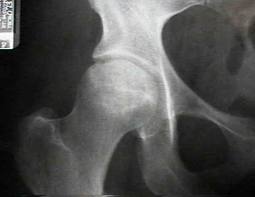

Dr. Kelley explained that Shawn had avascular necrosis — deterioration of the bone due to blood loss — which had caused the heads of his femurs, his leg bones, to collapse.

The cause of Shawn’s avascular necrosis is unknown, but he theorizes his time in the Marine Corps and his penchant for extreme sports such as skydiving may have contributed to his hip joints’ decline.